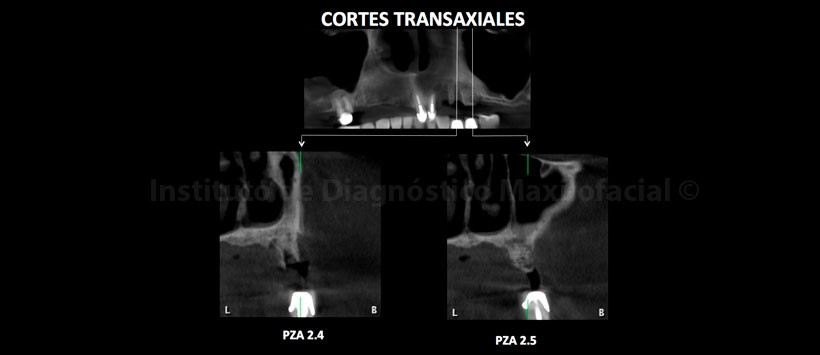

A la evaluación de la tomografía volumétrica (CBCT) en los cortes axiales (Figura 2, 3), coronales (Figura 4,5), transaxiales (Figura 6,7) y tangenciales (Figura 8), se aprecia proceso osteolítico de límites mal definidos, bordes difusos, localizado a nivel del maxilar superior del lado izquierdo, que se extiende en sentido mesio-distal desde la pieza 2.2 hacia los lechos alveolares de las piezas 2.3 y 2.4 y en sentido cefálico-caudal de la címa de reborde alveolar hasta el piso del seno maxilar a nivel de la zona de pieza 2.5. Se aprecia, presencia de secuestros óseos y reacción periostal en la tabla ósea vestibular y en zona del piso del seno maxilar.

En las reconstrucciones 3D se representa la lesión ósea que involucra los lechos alveolares de piezas 2.3 y 2.4 y además la presencia de secuestros óseos (Figura 9,10 y 11).